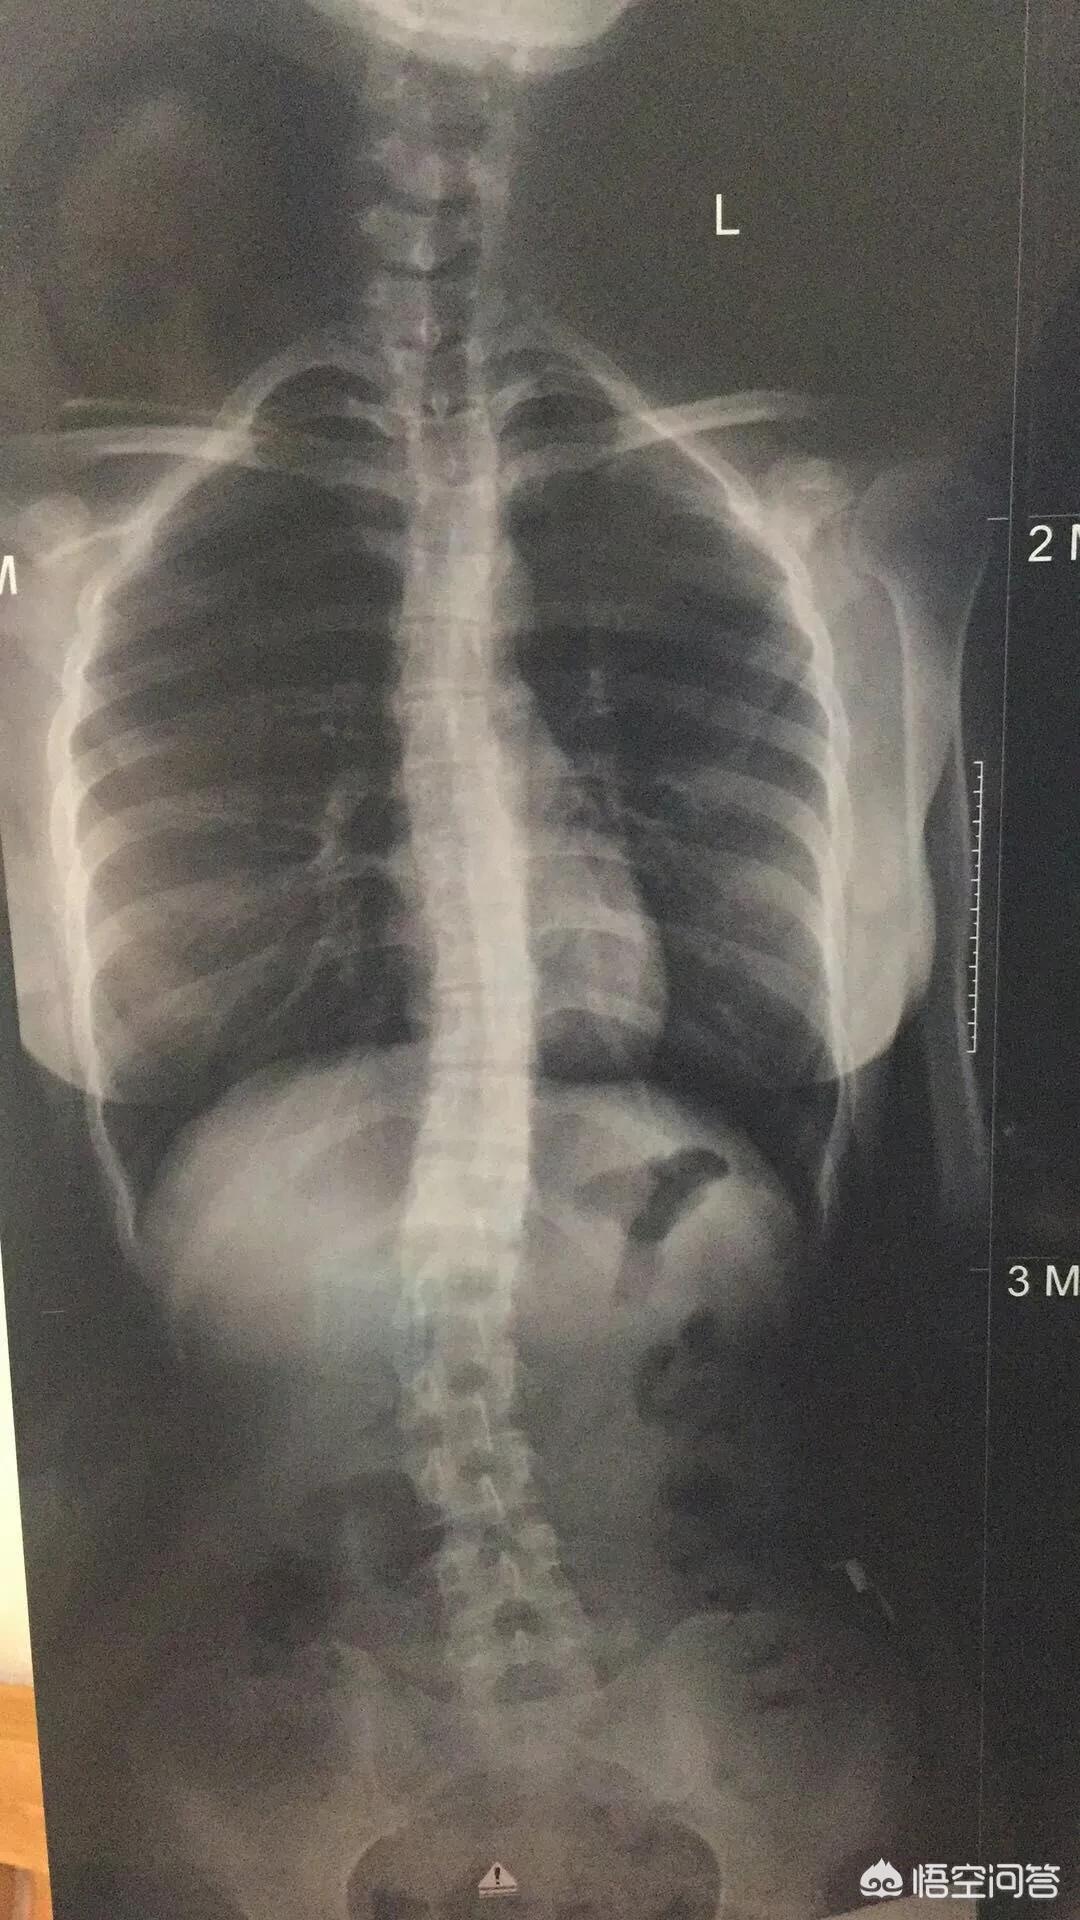

2,代偿性脊柱侧弯,就是指没有先天性椎体发育缺陷,但在后天生长中,太多的不良习惯,而出现脊柱侧弯,通常角度不大,但患者有明显的疼痛不适,80%的患者多发于快速生长的青春期。

而在中国,因为青春期时正是教育压力最大的时期,久坐学习时间过长,也是我国青少年脊柱侧弯高发的主因。

在深圳某高中抽查时,就发现过70%的少年存在不同程度的脊柱侧弯,可以说已经是仅次于近视的第二大青少年健康问题。